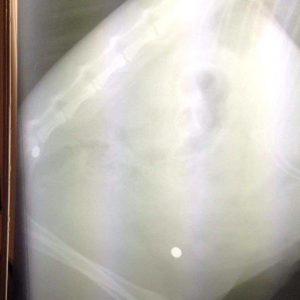

Bei der Röntgenuntersuchung fanden sich insgesamt vier Projektile in dem Tier, die eindeutig auf eine Luftwaffe hinweisen. Außerdem hat sie im linken Vorderlauf eine Schraube stecken, die mit Wucht eingedrungen sein muss. Womöglich durch eine selbstgebaute Waffe.

Es befindet sich jeweils ein Projektil direkt an der Wirbelsäule und eines auf dem Schädel. Diese Verletzungen sind alt, die Hautwunden schon lange verschlossen.

Zwei weitere Projektile und die Schraube sind frische Verletzungen! Ein Projektil drang durch einen Hinterlauf ein, ein weiteres befindet sich in der Nähe des Zwerchfells.